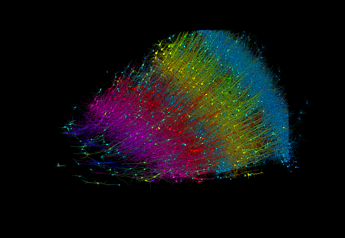

(Adnkronos) – Un frammento di cervello umano, grande meno di un chicco di riso, è stato ricostruito in 3D e mappato per la prima volta. Ci sono riusciti i ricercatori dell’Università di Harvard e Google Research dopo 10 anni di lavoro. Lo studio è stato pubblicato su ‘Science’. La grandezza del frammento è di un millimetro quadrato, che potrebbe essere piccolissimo, ma contiene 57mila cellule, 230 millimetri di vasi sanguigni e 150 milioni di sinapsi, che in termini di ‘big data’ vuole dire 1.400 Terabyte di dati da analizzare. La ricostruzione in 3D mostra “con realismo dettagliato ogni cellula” del cervello umano “e la sua rete di connessioni neurali in un pezzo di corteccia temporale umana grande circa la metà di un chicco di riso”, si legge nello studio.

Oggi abbiamo quindi il ‘cablaggio’ estremamente complesso del cervello dei mammiferi. Infatti, i ricercatori hanno sottoposto ogni sezione di questo frammento ad analisi tramite microscopio elettronico, ottenendo centinaia di milioni di immagini che sono state poi ‘cucite’ insieme per ottenere la mappa tridimensionale.